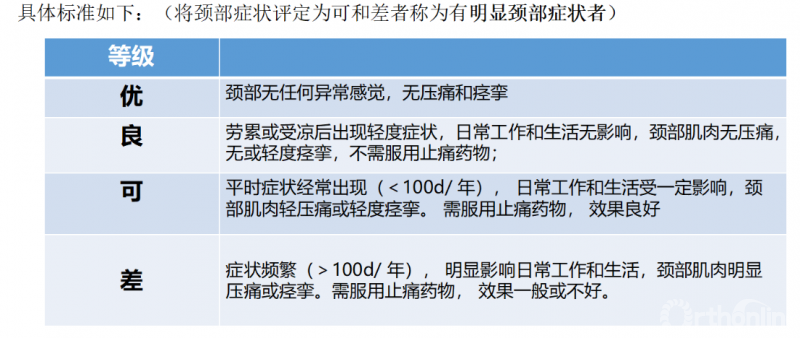

(二)轴性症状的评价标准

AS量化标准:

最初根据症状轻重分为三级:

I级(无或轻微):颈肩无明显不适或仅有轻微酸胀;

Ⅱ级(明显):颈肩部酸胀感显著,颈项易疲劳,头有下坠感;

Ⅲ级(严重):颈部疼痛严重,极易疲劳,借助颈围等支具支撑颈项。

随着重视的不断提升,多种量化标准开始涌现,主要包括:轴性症状疗效标准评定(曾岩标准)、日本应庆大学(颈椎AS评分表)、Honoso标准、Tsuji评分系统。

①轴性症状疗效标准评定(曾岩标准)

是对患者现阶段颈部各种症状包括疼痛、酸胀、无力、僵硬及“落枕”样感觉等进行分析,根据其对工作和生活的影响程度,以及客观体检颈部椎旁肌和斜方肌是否有痉挛和压痛,共分四级。